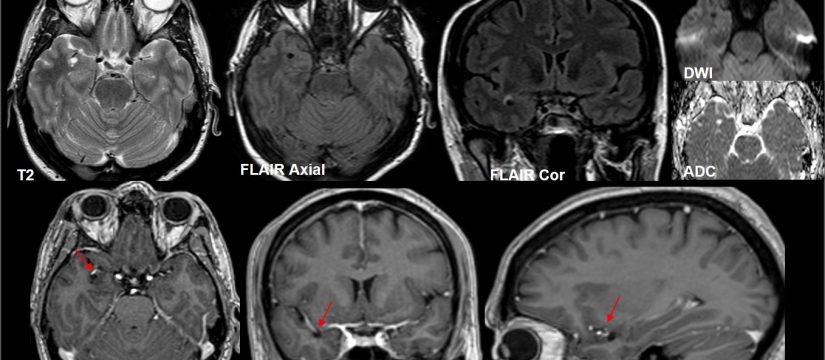

Mujer de 69 años de edad, con un cuadro de 7 meses de inestabilidad cefálica y de la marcha. Se realiza una RM craneal inicial, que es normal. Progresivamente, la síntomatología empeora, añadiéndose desorientación, alucinaciones, mioclonías y deterioro cognitivo. Se repite RM craneal por empeoramiento clínico progresivo.